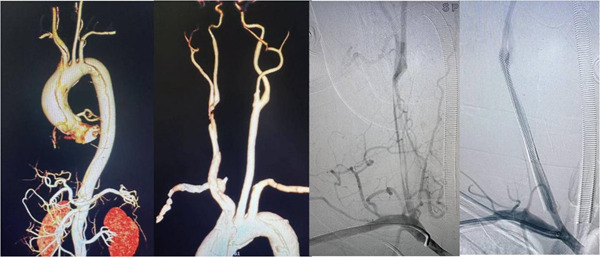

第一关,是微创通脑。蒋正副教授团队率先操作,摆在他们面前的,是层层技术难关:受主动脉夹层影响,只能从患者桡动脉通路开通血管,但即使在B超定位下,桡动脉和肱动脉也几乎看不到搏动,穿刺难度堪比“闭着眼找地下的细钢丝”;从手腕的血管通到颈部的颈动脉,全程要避开撕裂的主动脉,稍有不慎就会导致血管破裂大出血;更棘手的是,夹层患者术前不能用抗血栓的药物,支架植入后稍有差池就会形成血栓,前功尽弃。

凭借极致的精准操作,团队通过手术切开暴露桡动脉,成功建立介入治疗通路,顺利在堵死的右侧颈动脉里植入2枚支架,把被夹层压扁的血管完全撑开。术后造影显示,患者右侧大脑的血流瞬间恢复通畅,第一关圆满成功。

神经介入手术收尾的瞬间,宋国宝教授团队立刻无缝接力,开启第二关的心脏拆弹。团队在低温麻醉、人工心肺机的支持下,精准完成了撕裂血管的全程修复:换掉了从心脏出口到主动脉弓的全部撕裂血管,补好了被撕坏的冠状动脉开口,同时修复了受损的心脏瓣膜,彻底拆除了心脏上的致命“炸弹”。